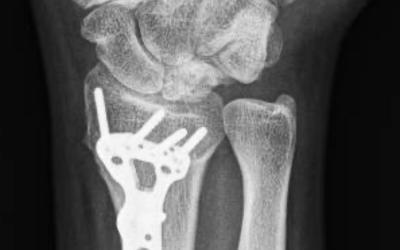

Enfermedad de Kienböck: qué es, síntomas y tratamiento La enfermedad de Kienböck es una patología poco frecuente de la muñeca que afecta al hueso semilunar, uno de los ocho huesos del carpo. Fue descrita en 1910 por el médico austriaco Robert Kienböck y, aunque es...